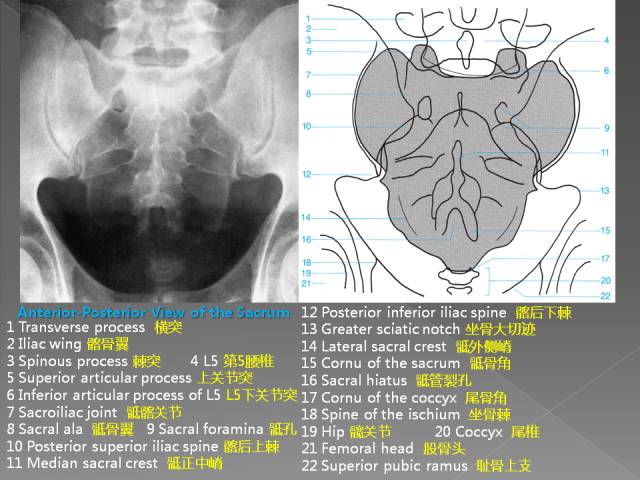

1、正位片

腰椎正位片,可显示腰椎有无侧凸,两侧横突大小有无异常(如第五腰椎横突肥大),有无移行椎(见后)、隐裂、棘突偏歪,椎间隙两侧是否等宽,椎弓根、关节突关节形状,椎弓根间距(椎管横径)大小等。

(5)还可观察两侧腰大肌阴影是否清晰。腰大肌阴影模糊、膨胀,常是腰大肌脓肿(结核)的表现。